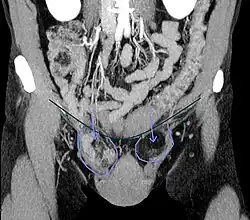

Leistenbruch (rechte Seite des Körpers)